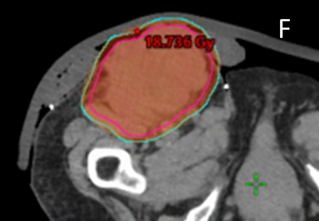

F Screen shot F shows the supine planning CT scan with an axial cut through the groin (as in C), but with the dosimetry with the dose wash set to the phase 1 prescription dose of 18Gy showing good conformity to the PTV. This plan was accepted by the RO.

G The astute nurse asked for the screen shot G which shows the same scan but with the dosimetry with the dose wash set to half the phase 1 prescription dose that is, 9 Gy. The 9 Gy covers the skin medial (white arrow) and lateral (red arrow) to the tumour mass where the acute reaction of erythema in normal skin was observed. The nurse was able to explain to the patient, the family, and the institution that the red skin was radiation dermatitis, and that the exudate was tumour necrosis. This was a radiation reaction and not infection, saving the patient from an unnecessary course of antibiotics. Nursing interventions could include a swab to rule out any underlying infection and education for nursing home staff about the tumour necrosis exudate and its appropriate management.